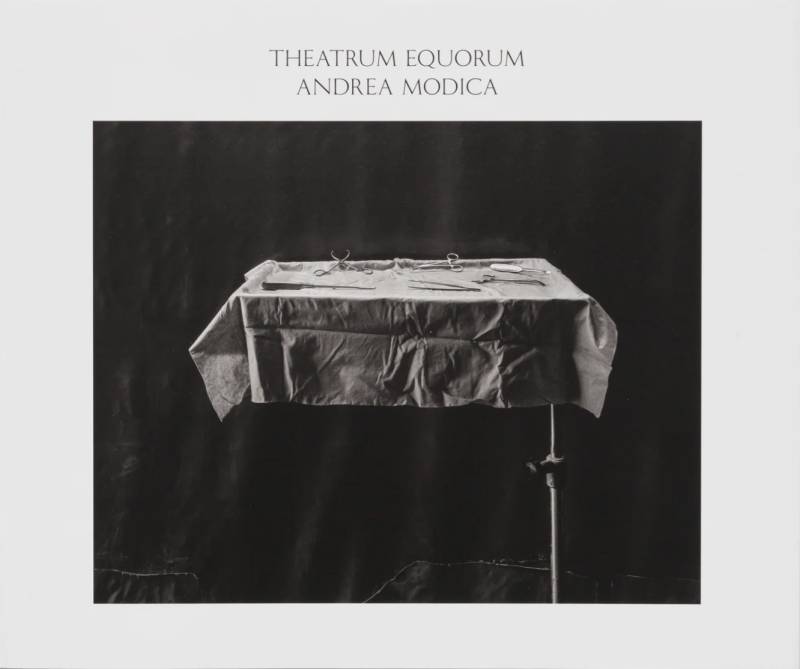

The result of more than eight years of intense work in Italy and elsewhere, Theatrum Equorum is acclaimed photographer Andrea Modica’s latest monograph with TIS books.

As the title indicates, Modica’s interest lies in the drama of the horse – but her approach is one that completely upends expectations for such an exploration. Using her trademark 8 in x 10 in large format camera, she made these photographs at a renowned horse clinic in Bologna that attracts remarkable and often very valuable animals for a range of medical procedures including, among other things, fracture repairs, emergency colic intervention and dental work.

“When I was invited to witness an operation, I was immediately drawn to the contrast of these magnificent animals rendered so vulnerable,” Modica says. “I instantly wanted to investigate with my camera.” She began the project by making pictures of the horses in their post-operative recovery rooms: simple padded stalls with overhead windows that produce a lovely, soft light. To protect the animals as they emerge from anesthesia, the floors are carefully covered with the surgeon’s shredded junk mail, old medical journals, and art magazines. “The stalls are at once theatrical stages and humble boxes. In my photographs the horses are in an anesthetic sleep,” the artist notes. “There’s something sacred about the animals and the process of being able to go through this with them—a state of extreme vulnerability for an animal of that power.”